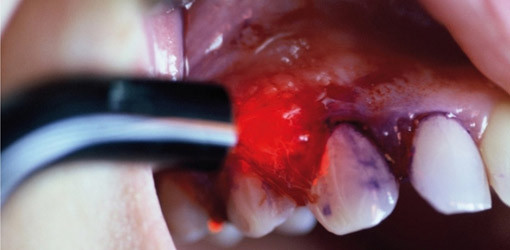

Foto: © Dr. med. Frank Wolfgang Förster

Monochromatisches Laserlicht kann erfolgreich bei der Inkorporation von Implantaten, beim Weichgewebsmanagement oder bei der Periimplantitistherapie eingesetzt werden. Voraussetzung für den Einsatz eines Lasers ist der Erwerb eines Zertifikates, das zur Anwendung durch den Implantologen legitimiert.

Implantologie und Laserzahnheilkunde weisen große Schnittmengen auf: Monochromatisches kohärentes Laserlicht stellt einen entscheidenden Bestandteil bei der Behandlung der Periimplantitis dar. Der orale Biofilm lässt sich mit Hilfe eines geeigneten Lasers sicher und effizient vaporisieren. Diese evidenzbasierte Erkenntnis hat zur Einführung eines Moduls „Laser und Periimplantitis“ im Rahmen des Curriculum Implantologie der DGZI geführt. Der Wochenend-Kurs steht auch Kolleginnen und Kollegen offen, die nicht das gesamte Curriculum absolvieren, sondern sich speziell für diese Veranstaltung interessieren.